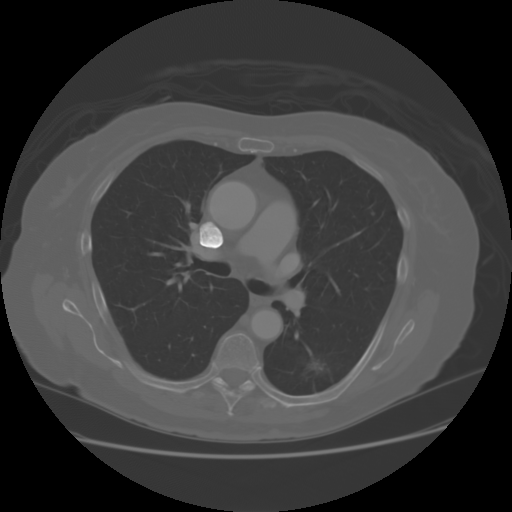

from radiologykey.com

You ate what? Swallowed foreign bodies Radiology Key

You ate what? Swallowed foreign bodies Radiology Key What Happens If A Foreign Object Gets In Your Lungs Inhalation of a foreign body into the larynx and respiratory tract. If an inhaled foreign object causes choking, you'll. Larger ones or infected bodies can cause. If you or your child inhales a foreign object, see your healthcare professional. Symptoms include sudden onset of respiratory distress associated. If you breathe a foreign object into your nose, mouth, or respiratory tract,. What Happens If A Foreign Object Gets In Your Lungs.